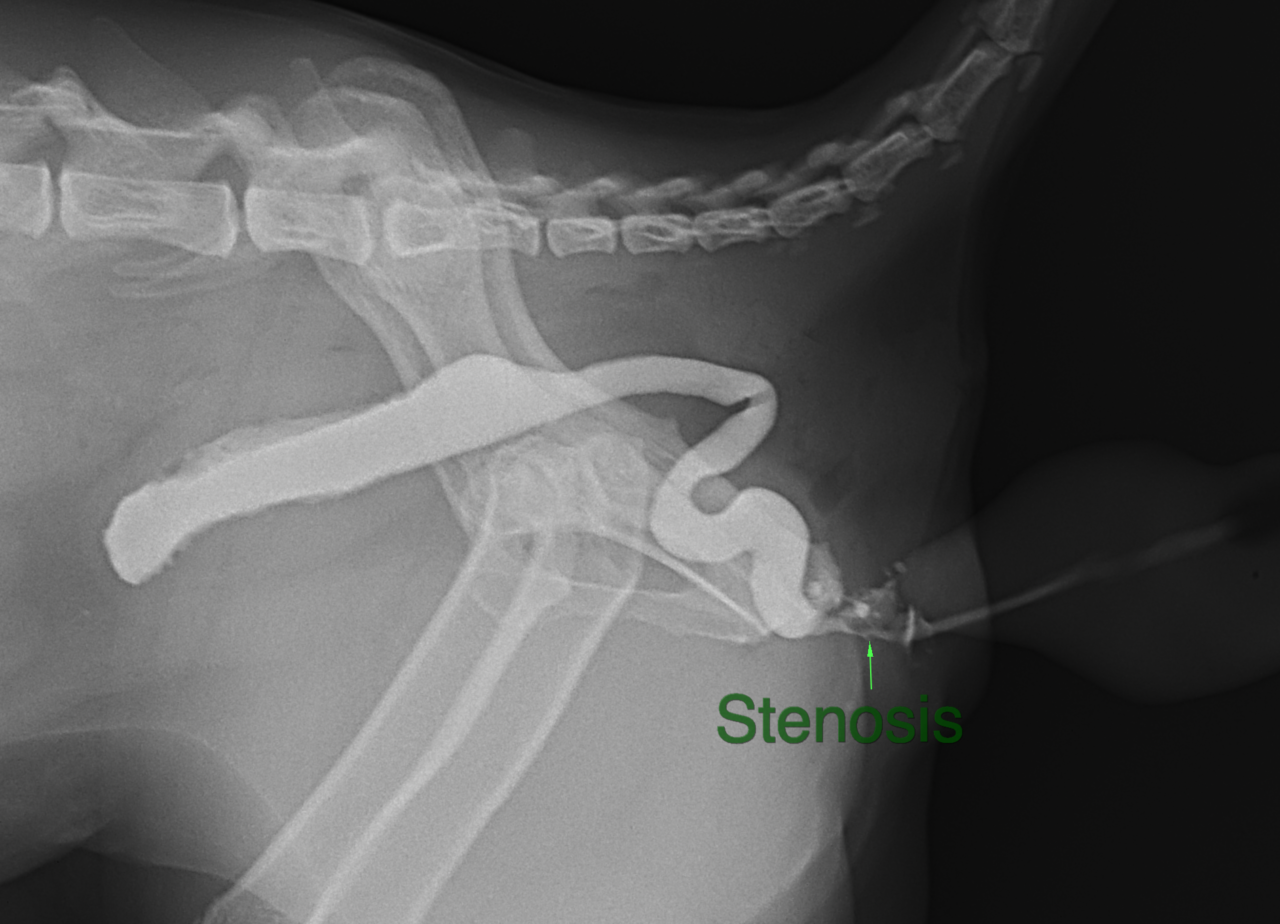

過去にかかりつけ医で会陰尿道瘻設置術を実施した猫ちゃんが、再び排尿が困難となって来たとのことで来院されました。かかりつけ医よりセカンドオピニオンがありました。尿道造影を行うと皮膚と尿道フィステルを形成した部位で狭窄と皮下に尿が漏れが生じているようです。恥骨部分に骨切り術を行い骨盤腔より尿道を誘導し、皮膚と再縫合を実施しました。会陰尿道瘻設置術の術後の合併症の一つと考えられております。